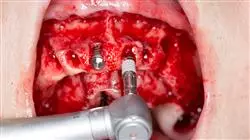

Модуль 4. Базовая хирургическая техника в области имплантологии

• Описать основные хирургические процедуры: Разрезы, типы лоскутов, наложение швов

• Объяснить хирургические процедуры экстракции, френэктомии

• Объяснять одноэтапные и двухэтапные хирургические процедуры, готовить операционное поле и осваивать протоколы стерилизации